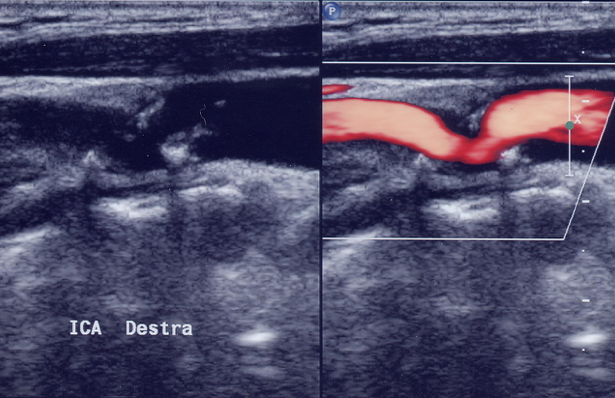

Riusciamo a “guardare” dentro le carotidi mediante un semplice esame non invasivo: l’ECOCOLORDOPPLER.

L’esame permette di valutare “la salute” delle nostre carotidi, le iniziali alterazioni della parete arteriosa (misurando l’ispessimento dello strato intermedio ed interno del vaso definito IMT), la presenza di placche ateromasiche e la % di restringimento del vaso.

Ecocolordoppler: placca all’interno della carotide interna |

Il riscontro inoltre di restringimenti severi della carotide (stenosi superiori al 75 %) permette di identificare soggetti ad altissimo rischio di ictus cerebrale, patologia purtroppo spesso silente senza iniziale sintomi ma con drammatiche conseguenze una volta verificatosi.